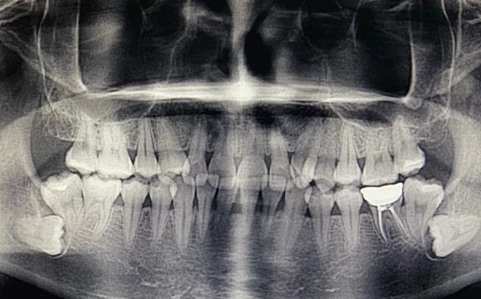

1、反復炎癥:智齒出牙不完整,齦冠覆蓋后側部分形成冠周袋。不注意個人衛生,局部軟組織往往會發炎,出現疼痛癥狀,所以需要拔掉智齒才能有效改善。

2、影響鄰近牙齒:如果牙齒生長位置不正確而擁擠,就有可能對鄰近牙齒造成損害,使咀嚼功能嚴重受損,因此需要拔除智齒。